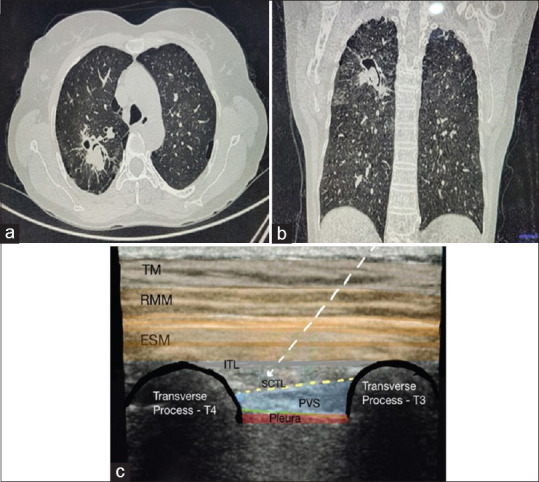

An Approach to Intraoperative Accidental Pulmonary Artery Transection and Role of Mid-Point to Transverse Process Interfascial Plane Block.